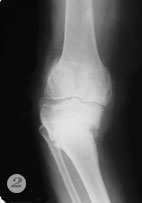

Пример №5 Эндопротезирование коленного сустава

1,2 до операции